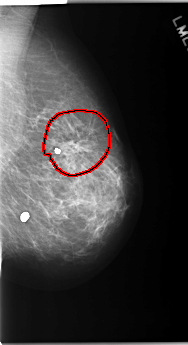

C_0171_1.LEFT_CC

FILE: C_0171_1.RIGHT_CC.OVERLAY

TOTAL_ABNORMALITIES 1

ABNORMALITY 1

LESION_TYPE CALCIFICATION TYPE PLEOMORPHIC DISTRIBUTION CLUSTERED

ASSESSMENT 4

SUBTLETY 4

PATHOLOGY MALIGNANT

TOTAL_OUTLINES 1

BOUNDARY